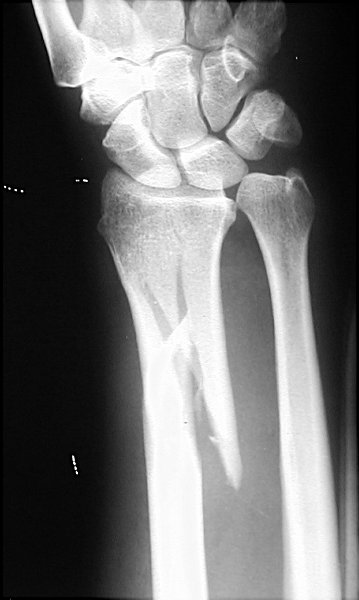

Return to Galeazzi's Fracture